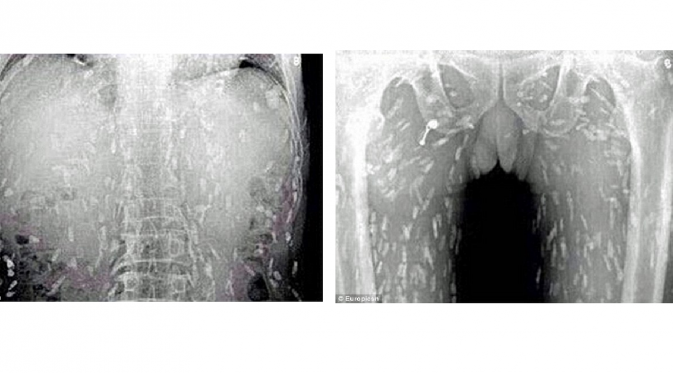

Dokter yang melakukan pemindaian pada tubuh pasien, menemukan kondisi menyeramkan karena cacing pita sudah memenuhi badan pria tersebut setelah ia banyak makan sashimi yang merupakan makanan ala Jepang berupa irisan daging ikan mentah.

Dokter yakin, ikan mentah yang dikonsumsi penderita telah terkontaminasi. Pasien akhirnya dirawat di Guangzhou No. 8, Rumah Sakit Rakyat di Provinsi Guandong di China timur.